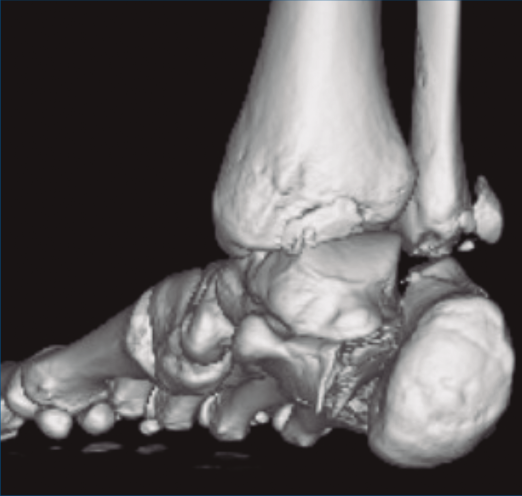

Figura 1. Luxación del astrágalo en mortaja tibioperonea, fractura maléolo peroneo y espacio subperoneo ocupado por calcáneo.

Figura 2. Fractura maléolo peroneo y tibial posterior. Trazo entre fragmento anteromedial y posterolateral.

Figura 3. Desplazamiento entre fragmento anteromedial (sustentaculum tali) y posterolateral (tuberosidad).

Se trata de un varón de 19 años que ingresa en reanimación tras precipitarse desde una altura de aproximadamente 10 metros. El paciente presenta una fractura estallido de L3 con afectación del canal medular junto con una fractura del vértice inferior de L4, así como una fractura luxación de calcáneo, asociada a una fractura del maléolo peroneo y del maléolo tibial posterior (Figuras 1 a 6) diagnosticadas mediante TC total body (por eso no se dispone de radiografías simples al momento del ingreso). Como podemos comprobar, se trata de una fractura de doble trazo de tipo hundimiento/depresión de la carilla articular (Figuras 5 y 6).

Figura 4. Luxación fragmento posterolateral.

Figura 5. Fractura maléolo peroneo, luxación astrágalo, fractura de doble trazo en calcáneo.

Figura 6. Fractura de doble trazo; se evidencia afectación de la articulación calcaneocuboidea.